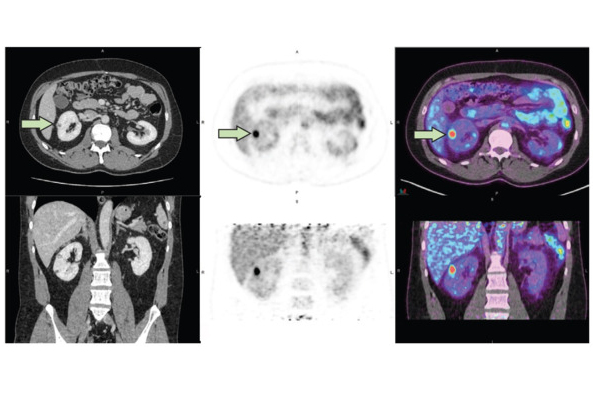

Examples of native T1 and T2 mapping in the reference group and renal mass cohorts with region of interest (ROI) delineation. A: Native T1 mapping (left) and T2 mapping (right) coronal raw images of normal kidneys. Three oval ROIs measuring 0.30cm2 were manually drawn at the same symmetrical location of the left and right kidneys, including the superior, middle, and inferior pole of the cortex. B: Native T1 mapping (left) and T2 mapping (right) coronal image of an oncocytoma of the upper pole of the right kidney (maximum diameter: 3 cm). A freehand circular ROI in the tissue part of the mass was set at 1.0cm2.Images courtesy of Dr. Remy Henry, Prof. Catherine Roy, et al, and European Journal of Radiology.

The group recorded the renal cortex values of 125 patients with normal kidneys (reference group) and 75 patients with renal masses on a clinical 3-tesla MRI unit (Ingenia CX, Philips) and a standard 32-channel torso phased-array coil using T1m and T2m sequences. For the quantitative evaluation, measurements were performed by delineating regions of interest (ROIs) on T1m and T2m sequences in the renal cortex of the reference group and in renal masses.